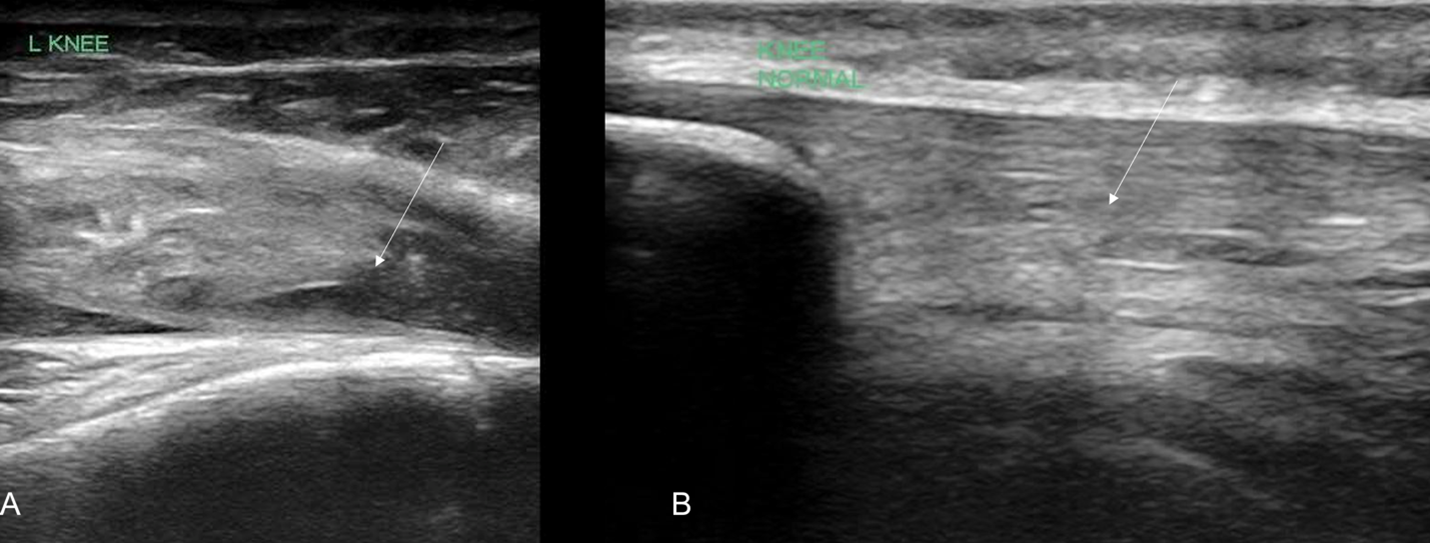

In our case report, we successfully identified key features suggestive of tibial tubercle fractures: disruption of the patellar tendon, posterior acoustic shadowing of a bone fragment, and a large joint effusion. To perform knee ultrasound, the linear probe should be used and placed inferior to the patella in sagittal plane. The patellar tendon should be visualized in two planes, fanning through it completely (Video 1), and compared to the contralateral normal knee. (Figure 4) Abnormal findings suggestive of epiphyseal fractures include disruption of the tendon, an increased hypoechoic space adjacent to or posterior to the tendon (suggestive of either hemarthrosis or a hematoma), or a hypoechoic zone (ie, posterior acoustic shadowing due to an avulsed bony fragment).3,4

Figure 4: A) Ruptured tendon (arrow) in comparison against (B) contralateral knee indicating the normal continuous tendon fibers (arrow)